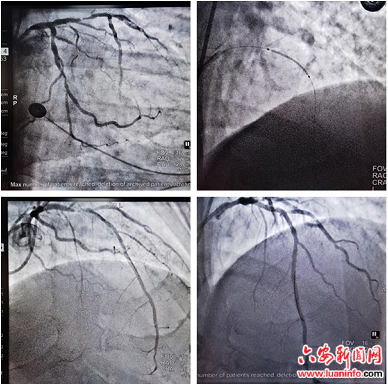

近日,市四院心血管内科团队为一名冠心病患者成功完成冠脉支架植入术,手术在孙自海主任和张传扩主任的共同努力下顺利开展。术后患者胸痛症状消失,血管造影显示支架贴壁良好,血运成功再建,目前恢复良好。

据了解,冠脉支架植入手术是近20年发展起来的冠心病治疗新技术,比药物治疗效果好,比开胸手术创伤小,其过程是:穿刺外周血管建立通路,在X光透视监视下将导管送达冠状动脉开口处,用特殊的传送系统将支架输送到病变部位,加压释放支架后撤出导管,结束手术。病人在局部麻醉的情况下接受手术,整个过程完全清醒、无明显痛苦。(宣传科)